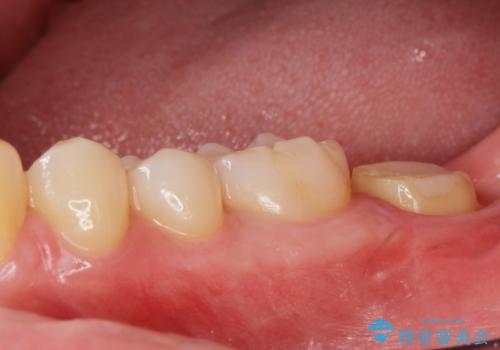

他院での治療に不信感 虫歯除去後のジルコニアクラウン

神経をとる処置をされた形跡がありましたがまだ虫歯が残っていたので全て取り除き、壁を立てて根管治療ができる状態にして、根管治療・ジルコニアクラウンで治療を行いました。

- ジルコニアクラウン・仮歯 12.1万円 根管治療(イニシャル)・ファイバーコア 13.2万円費用は治療当時の料金となります

虫歯除去、根管治療は拡大鏡やマイクロスコープを用いて治療を行っています。